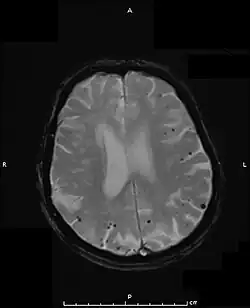

Klinisch stützt sich die Diagnose auf das radiologische Vorliegen von einzelnen oder multiplen lobären Blutungen an der Rinden-Mark-Grenze oder von Mikroblutungen im Gehirn ohne andere wahrscheinlichere Ursache.[3][14] Das Vorliegen einer zerebralen Amyloidangiopathie wird als wahrscheinlich angesehen, wenn in der Vorgeschichte mindestens zwei Blutungen ohne andere erkennbare Ursache vorliegen. Man geht davon aus, dass zwischen 5 und 12 % aller intrakraniellen Blutungen bei Patienten über 55 Jahren durch eine zerebrale Amyloidangiopathie verursacht sind.